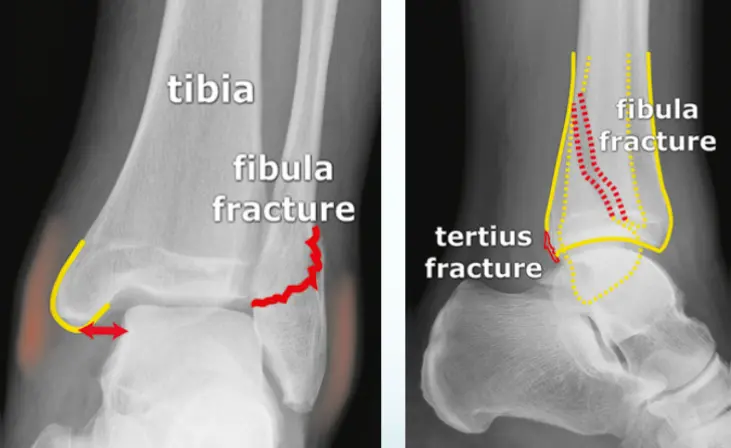

fracture distal fibula

Patient: 32âyearâold male with a severe twisting ankle injury â painful, swollen and unable to stand.

Findings

- Site: lateral malleolus

- Fracture type: simple

- Fracture line: spiral

- Displacement: gap medially

- Special issue: possible ruptured deltoid ligament

- Site â Bimalleolar ankle fracture

- Type â C (fibular fracture above the syndesmosis); medial malleolus simple

- Fracture line â medial malleolus transverse; lower fibula complex (comminuted)

- Displacements â medial malleolus & talus shifted laterally

- Special issues â syndesmosis injured; intraâarticular fracture needs anatomical reduction (ORIF)

- Site â Medial malleolus intact; fibular fracture present.

- Fibular fracture â TypeâŻB (located at the level of the syndesmosis), simple pattern with an irregular transverse fracture line.

- Displacement â Talus shifted laterally.

- Special issues â Deltoid ligament ruptured; syndesmosis may be intact.

- Management â Requires anatomical ORIF and ligament repair.

Site: Medial malleolus

Type: Simple intraâarticular fracture

Fracture line: Vertical

Displacements

- Gap in joint line

Special issues

- Requires anatomical reduction and absolute stability

- Possible lateral collateral ligament injury